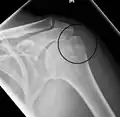

Proximal humerus fracture -

A displaced supracondylar fracture in a child